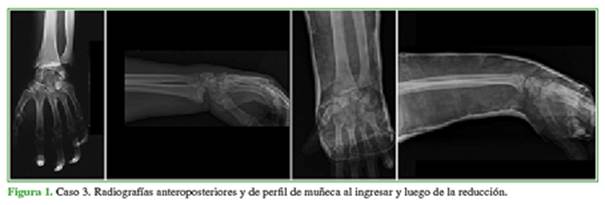

En la sala de emergencia, se tomaron radiografías anteroposteriores y de perfil de muñeca o antebrazo (Figura 1). Se registraron la edad, el sexo, el mecanismo de producción y las lesiones asociadas. Un paciente tenía una fractura del pilón tibial; otro, una fractura de fémur y tibia diafisaria, y otro, una luxofractura de Monteggia, lesión de partes blandas tipo herida con colgajo en muslo, fractura de falange del pie, segundo metacarpiano homolateral y traumatismo craneoencefálico grave que requirió el ingreso en la Unidad de Cuidados Intensivos por 14 días (Tabla 1).